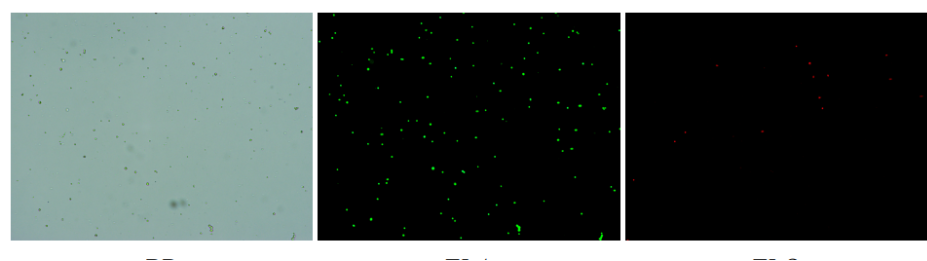

肝臟是人體代謝和解讀的器官,在體內(nèi)發(fā)揮氧化、儲(chǔ)存肝糖、合成分泌性蛋白合成等,肝臟也制造消化系統(tǒng)中之膽汁,人肝約有25億個(gè)肝細(xì)胞。但是解離肝臟組織懸液并不簡單,首先,肝臟代謝旺盛,離體后肝細(xì)胞無法進(jìn)行正常的有氧糖酵解,細(xì)胞活力會(huì)迅速下降,另外,肝細(xì)胞的線粒體很多,每個(gè)細(xì)胞大約有1000個(gè)左右,遍布于胞質(zhì)內(nèi)。因此,很難得到符合單細(xì)胞測序要求的單細(xì)胞懸液。百邁客生物在肝臟組織單細(xì)胞懸液制備方面有豐度的實(shí)操經(jīng)驗(yàn),開發(fā)了獨(dú)有的解離體系,下面來看實(shí)驗(yàn)結(jié)果:

實(shí)驗(yàn)結(jié)果

人膽管癌樣本,活性90.45%,結(jié)團(tuán)率7.2%

Tips: 肝實(shí)質(zhì)細(xì)胞經(jīng)過解離后因?yàn)槿毖醴浅H菀装l(fā)生凋亡,導(dǎo)致占比很低,如果老師關(guān)注肝實(shí)質(zhì)細(xì)胞的話,建議采用單細(xì)胞核懸液的方法。